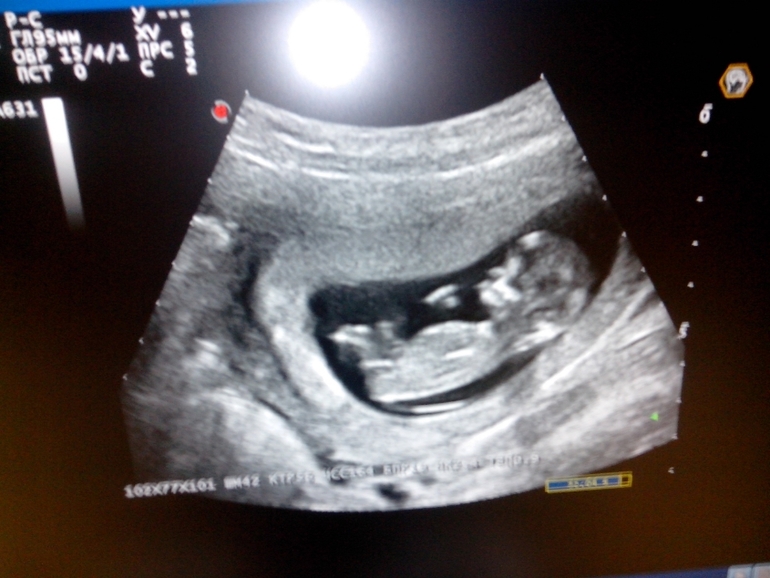

Наш 1-ый скрининг! Моя любимая детка, моя радость, моя жизнь!!!!!

Только сейчас увидела подпись после 2й фотки) У нас тоже очень активный малыш, прям как будто знал, что на него смотрят, показал себя во всей красе =) Узист сказал, что пол сейчас непонятен, но нам с мужем показалось, что мальчик!

у нас один малыш) с ней всё хорошо))) меня передали в руки Светланы Ивановны теперь)))теперь тоже будем ждать скрининг)))

я сама в растерянности с этими бугорками, но если честно мне это на столько не принципиально, самое главное он там такой активный - чувствует себя хорошо)))

Ну вот и сходили мы на УЗИ) на подходе экватор)